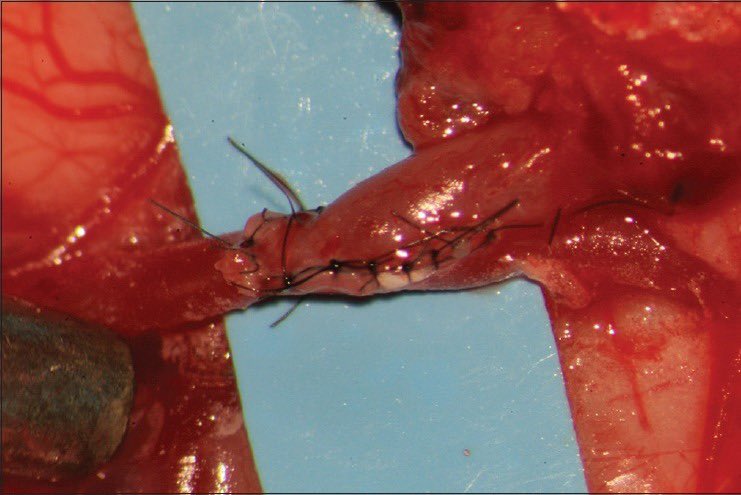

They undergo ventriculostomy placement. CSF analysis supports this with 64 WBC, 46 RBC, protein 58, Glucose 42, 51% neutrophilic. What is going on???

8/